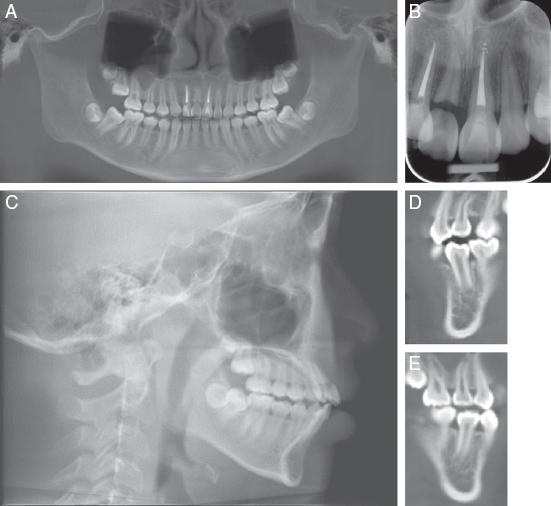

At the debonding stage, Class I canine and molar relationships were established, and the lower second molars had uprighted. The patient’s straight profile was preserved by careful retraction of her anterior teeth and the dental midlines coincided with her facial midline (Figure 11A-H). No signs of ankylosis, pathology nor periodontal problems were detected radiographically. The transplanted teeth exhibited an increase in root length and pulp canal obliteration was observed (Figure 12A-D). A good occlusion was achieved, and the patient was satisfied with the results of treatment.

(A) Posttreatment panoramic radiograph. (B) Periapical radiograph of autotransplanted teeth showing good root length and pulp canal obliteration. (C) Lateral cephalogram. (D) 4-year follow-up of the transplanted teeth showing adequate root lengths and optimal intra-crestal bone levels. Pulp canal obliteration was seen in both transplanted teeth.